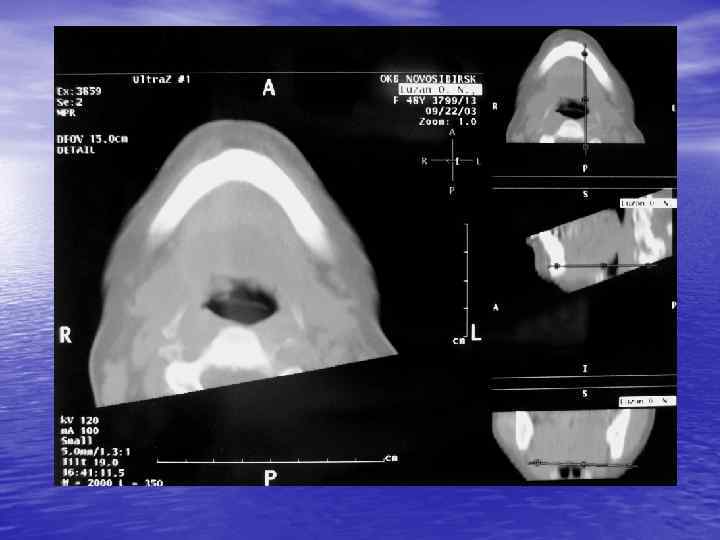

Процесс получения КТ изображения содержит три основных этапа: üизмерение, üреконструкция, üвизуализация. В настоящее время КТ можно использовать для визуализации любой части тела!

Преимущества спиральной КТ: ü Возможность проведения исследования с болюсным ü ü ü ü ü контрастированием Высокая разрешающая способность; Высокая скорость исследования; Получение высококачественных изображений костных структур; Возможность обследования всего тела; Возможность проведения исследования больных под наркозом; Возможность детальной оценки состояния крупных и периферических сосудов в условиях искусственного контрастирования; Высокая информативность метода при черепномозговых травмах в остром периоде; Ранняя диагностика ишемических и геморрагических инсультов; Метод выбора для диагностики заболеваний легких; Планирование лучевой терапии.